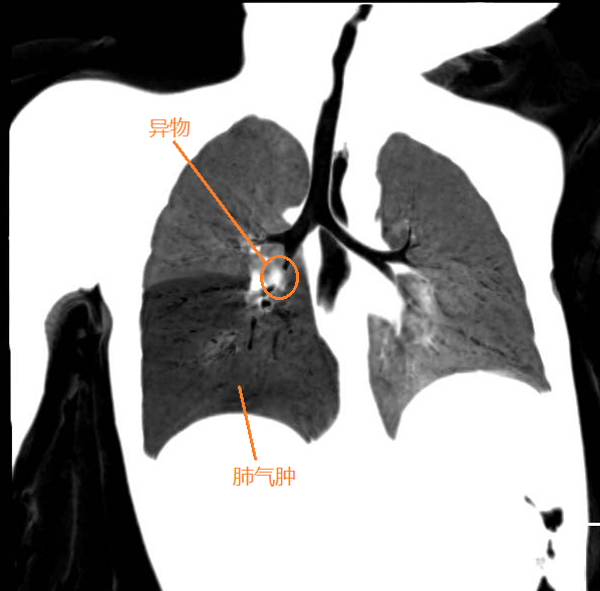

據悉,患兒在家吃橘子后出現煩躁、哭鬧,拒食的表現,便來到我院就診,耳鼻咽喉科韋順蓮醫師接診時發現小朋友的精神萎靡,呼吸稍急促,右下肺呼吸音減弱,而且近一周還有間斷的咳嗽癥狀。憑借多年的臨床經驗讓韋醫師一下子警惕起來,第一時間安排患兒做肺部CT及血常規檢查,CT顯示患兒的右側二級支氣管有低密度影,右下肺氣腫,原來是氣管中有異物。1歲幼兒該位置的氣管直徑只有4-7mm,一旦阻塞就很容易引起肺炎,現在已經出現肺氣腫,說明氣管內已經大部分被阻塞,情況十分危急。